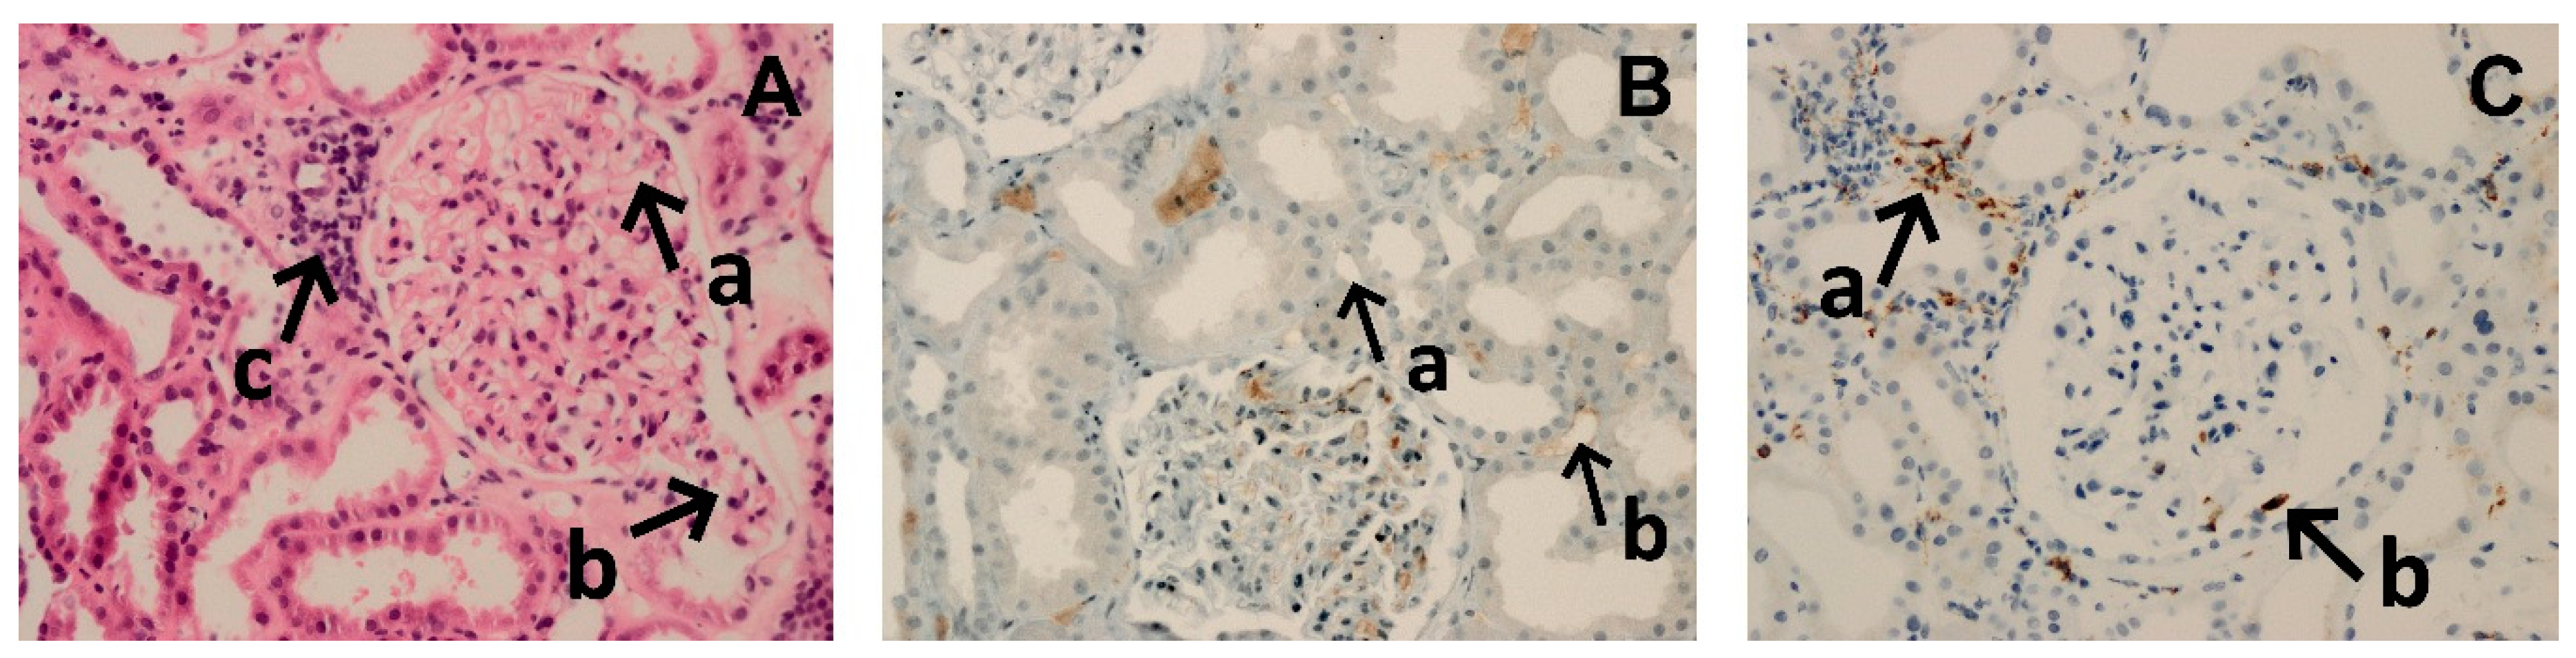

AMR was diagnosed based on the first protocol biopsy, performed at a median 10 (IQR: 9–10) post-transplant day (Table 2). Due to technical constraints, the histopatologic biopsy results were available after 2–5 working days. In the majority of patients, the CD4, CD8, and CD68 infiltration was predominantly seen, whereas CD20 staining revealed only single cells or scattered foci, except in three patients, in whom, CD20 clusters and/or groups were described (Figure 1). Hence, a primary AMR treatment started at median 19th post-transplant day. In eight patients, all three Banff criteria of AMR were fulfilled. In the next four patients, the suspected diagnosis was C4d-negative AMR. In one patient, results of pre-transplant single-antigen bead assay were not available, but the screening test for class II anti-HLA antibodies was positive (Table 2). Immediately after AMR diagnosis, the primary treatment was started as described above. One patient received only 3 out of 4 planned doses of bortezomib due to the observed gastrointestinal side effects. In the first three patients, PF treatment with fresh frozen plasma (FFP) was completed. In the next eight patients, FFP together with 5% human albumin was used, in the 1:1 volume proportion. The last two patients were treated with a modified protocol (bortezomib, ATG with total dose 5 mg/kg and IVIG single dose 1g/kg) as they initially received basiliximab induction, whereas we were not able to plan and perform PF sessions at that time. Besides, dialysis therapy was required in five patients before and partially also during the AMR treatment.

Figure 1.

Microphotograph presenting typical histologic findings in kidney transplant recipients with early antibody-mediated rejection. (A) Hematoxylin and eosin, magnification 100×. Interstitial edema (tubules are not back to back) with inflammatory infiltrates—asterisks, acute tubular injury (ATI) with the flattening of epithelium cells with the absence of brush border, acute tubular necrosis (ATN) with the tubular basement membranes denuded of epithelial cells, peritubular capillaritis (PTC-itis)—arrowheads, and hypoperfused glomeruli with microthrombi—arrow. (B) A diffused C4d staining pattern around peritubular capillaries. Magnification 200×. (C) Immunostaining demonstrating CD68-positive macrophages within glomeruli (a), interstitial space (b), and peritubular capillaries (c). Magnification 100×.